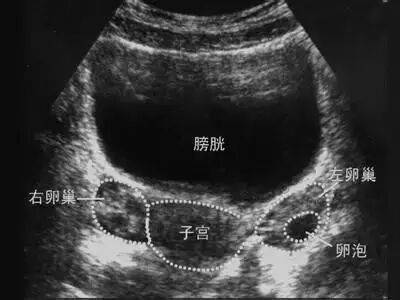

最简单、最直观的方法就是B超。

通过B超,医生能清楚的观察到卵泡,了解卵泡的大小、形态、生长速度、是否排卵。

因为卵子太小(直径只有0.2mm左右)无法用超声直接看到,只能通过卵泡的情况间接判断。

1、B超卵泡监测

通常因为卵泡早期发育的时候比较慢,可以2~3天监测一次,到后期卵泡会越长越快,就需要每天监测了。如果发现优势卵泡消失、明显缩小或皱缩5mm以上,内壁塌陷,子宫直肠窝可能会见到少量积液声像,就表示已经排卵了。